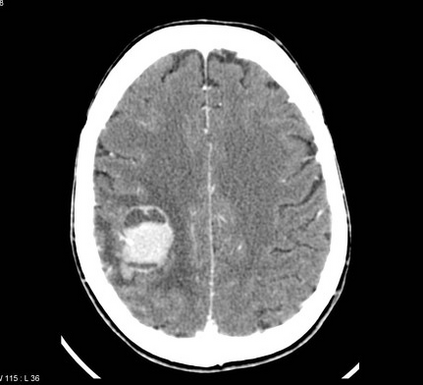

In this study, we aim to initiate the development of Radiology Foundation Model, termed as RadFM.We consider the construction of foundational models from the perspectives of data, model design, and evaluation thoroughly. Our contribution can be concluded as follows: (i), we construct a large-scale Medical Multi-modal Dataset, MedMD, consisting of 16M 2D and 3D medical scans. To the best of our knowledge, this is the first multi-modal dataset containing 3D medical scans. (ii), We propose an architecture that enables visually conditioned generative pre-training, allowing for the integration of text input interleaved with 2D or 3D medical scans to generate response for diverse radiologic tasks. The model was initially pre-trained on MedMD and subsequently domain-specific fine-tuned on RadMD, a radiologic cleaned version of MedMD, containing 3M radiologic visual-language pairs. (iii), we propose a new evaluation benchmark that comprises five tasks, aiming to comprehensively assess the capability of foundation models in handling practical clinical problems. Our experimental results confirm that RadFM significantly outperforms existing multi-modal foundation models. The codes, data, and model checkpoint will all be made publicly available to promote further research and development in the field.